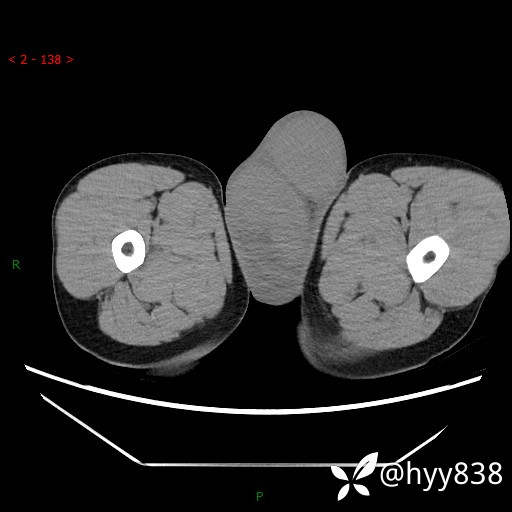

睾丸CT平扫